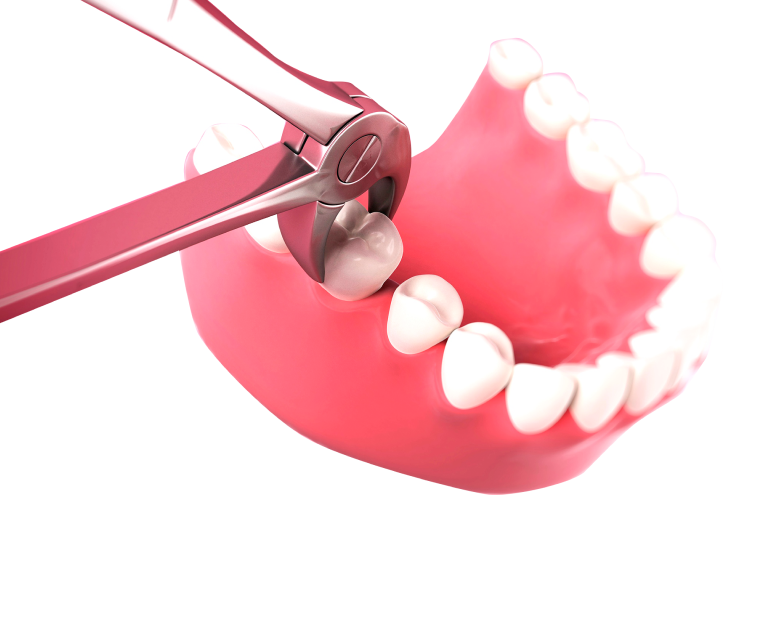

Мы не делаем разрезы, если позволяет ситуация и не удаляем зубы если их можно сохранить

Выбираем самые низкотравматичные методики лечения